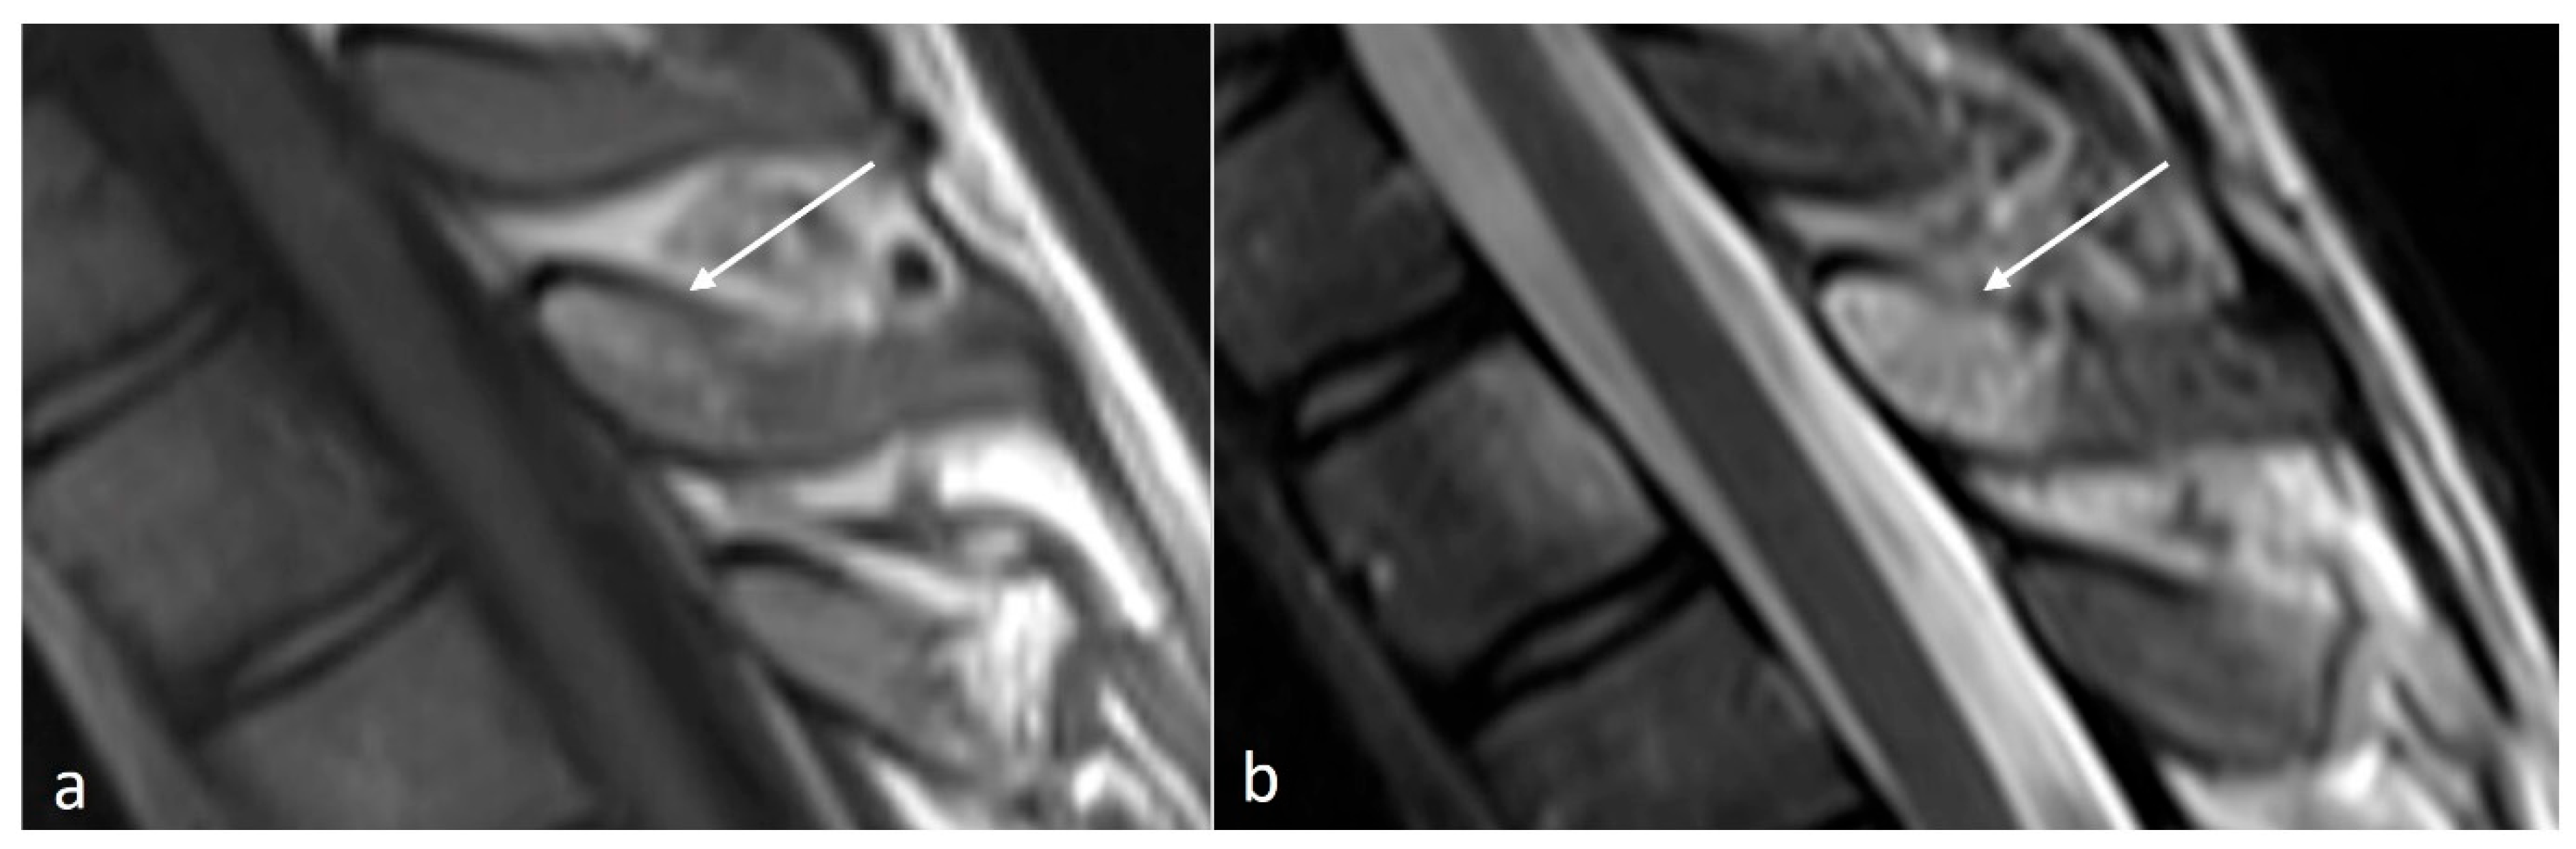

Characteristic imaging features include a close approximation of lumbar spinous processes (‘kissing spines”). CT may show reactive sclerosis, the resultant enlargement of the abutting spinous processes, and pseudoarthrosis formation. MRI can demonstrate interspinous bursal fluid as well as marrow oedema (Figure 1) [14]. Large bursal fluid collections can extend into the vertebral canal causing thecal sac compression.

Figure 1.

Sagittal STIR (short tau inversion recovery) image demonstrating Baastrup disease of lumber spinous processes (white arrow). Note the presence of reactive marrow oedema and sclerosis at the opposing surfaces of the spinous processes involved.